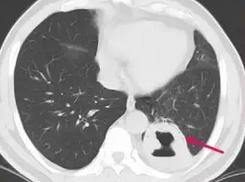

幸运2,男性56岁,老烟民,反复咳嗽咳痰1个多月,发现痰中带血1天:

看到这里,这张图片想必大家都会看了,厚壁空洞,空洞壁有平行的支气管,提示肺脓肿的可能,建议增强扫描!

对的,大家的看法没错!增强扫描显示病灶均匀强化,支持肺脓肿:

后来抗生素治疗后,病灶吸收!